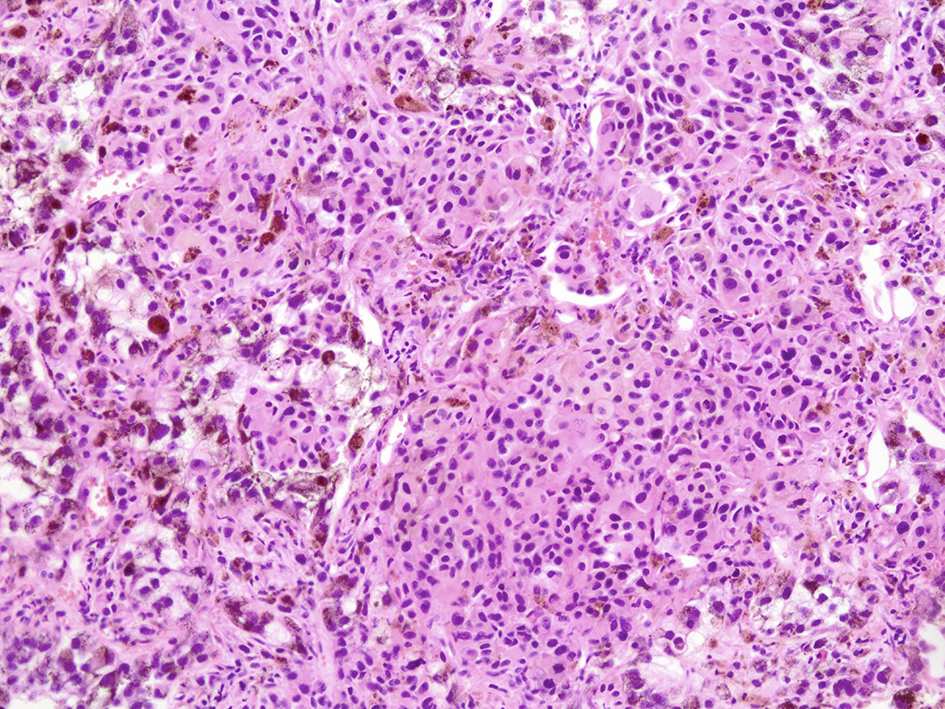

Microscopic examination of these organs revealed several interesting findings. Massive necrosis of normal hepatocytes and melanoma cells was observed in the liver. The lesion was composed of two parts: 1) centrilobular necrosis without bleeding; and 2) perilobular necrosis with hemorrhage (Fig. 7). Extensive necrosis was observed within the largest pulmonary tumor (Fig. 8), unlike the biopsied specimen taken antemortem (Fig. 9).

![]() Click for large image | Figure 8. Microscopic view of lung lesion on autopsy. Lung metastasis with diffuse necrosis taken by autopsy was shown. |